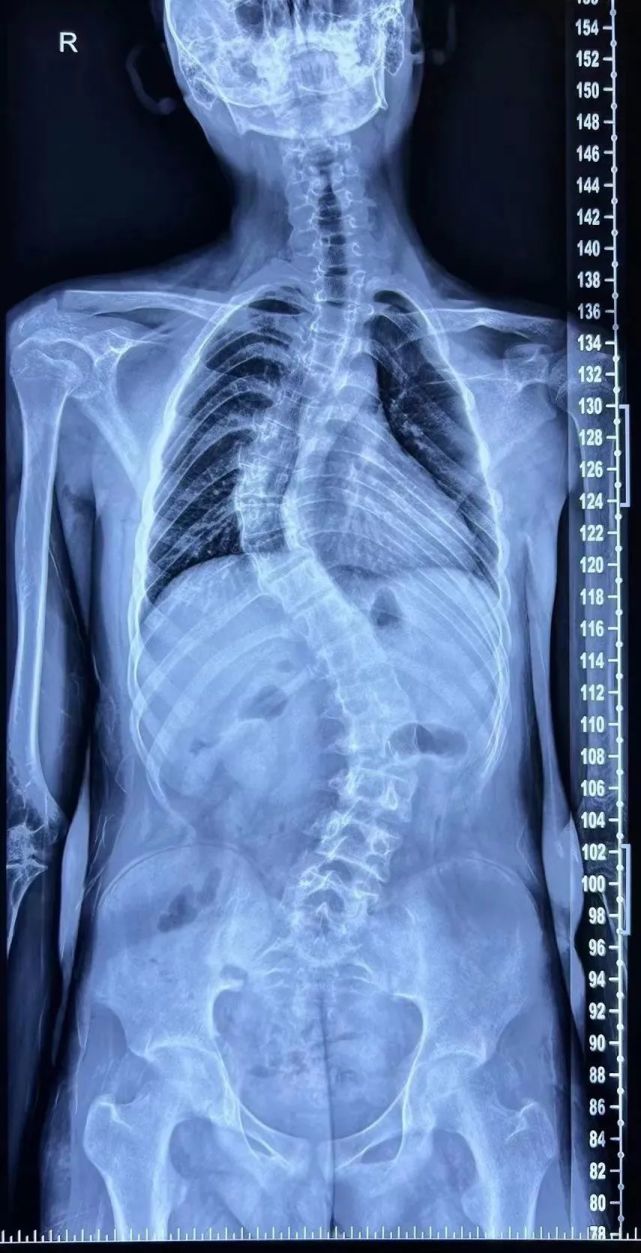

超过90度我们就叫重度脊柱侧弯,超过100度是极重脊柱侧弯

实录我陪女儿治疗脊柱侧弯的这三年